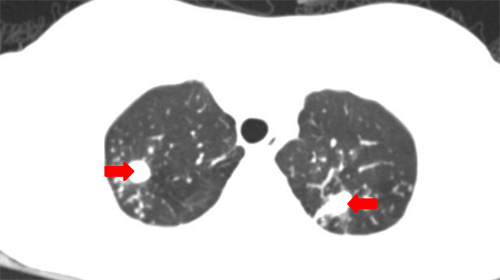

CT示小美(化名)双肺有多发病灶

据小美的母亲王女士介绍,小美于5个月前出现双下肢红斑,偶尔伴有瘙痒,带着孩子辗转市内多家医院就诊,考虑“结节性红斑”,给予激素类药物内服及外敷。小美病情刚开始有好转,但随后逐渐加重,反复出现下肢皮肤溃疡、坏死、流脓,双下肢还留下了褐色瘢痕、痂皮,并且体重明显下降,发热不退。王女士心急不已,带着小美辗转到了省级医院皮肤科就诊,经过一系列检查后发现小美的皮肤问题只是冰山一角,肺部也有多发病灶,考虑结核可能性大,为了得到更规范的诊治,小美转入香港马会app 学生儿童结核科接受住院治疗。